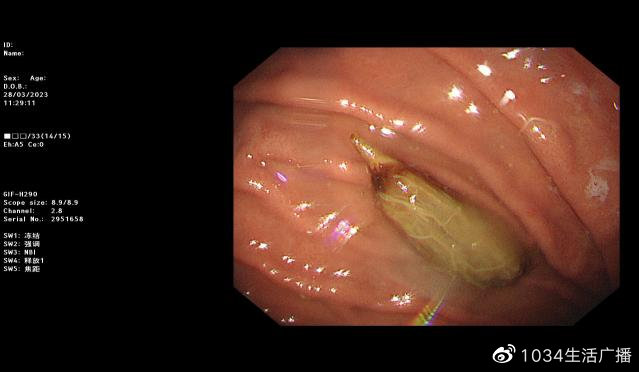

沈阳市第四人民医院消化内镜中心为徐女士进行了胃镜检查:发现枣核尖端已经将胃窦黏膜刺破出现溃疡,如果再晚来几天,枣核极有可能把胃壁刺穿、造成穿孔。医生应用异物钳将异物取出体外。